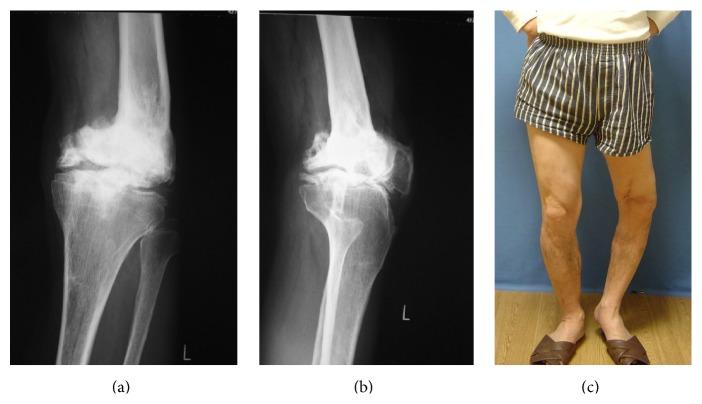

Introduction. The main indication for knee arthrodesis in tumor surgery is a tumor that requires an extensive resection in which the joint surface cannot be preserved. We report a patient that had knee desarthrodesis 41 years after giant cell tumor resection followed by a knee arthrodesis. This is the longest reported follow-up after desarthrodesis and conversion to total knee arthroplasty (TKA), almost ten years. Case Report. A 71-year-old man with a distal femoral giant cell tumor had undergone a resection of the distal femur and knee arthrodesis using Kuntscher nail in 1962. In July 2003 he experienced gradually increasing pain of his left knee. We performed a desarthrodesis and conversion to TKA in 2005. The postoperative period passed uneventfully as his pain and gait improved, with gradually increasing range of motion (ROM) and no infection. He now walks independently, with no brace or contractures. Conclusion. Desarthrodesis of the knee joint and conversion to TKA are a difficult surgical choice with a high complication risk. However, our patient's life style has improved, he has no pain, and he can ascend and descend stairs more easily. The surgeon has to be very meticulous in selecting a patient for knee arthrodesis and counseling them to realize that their expectations may not be achievable.